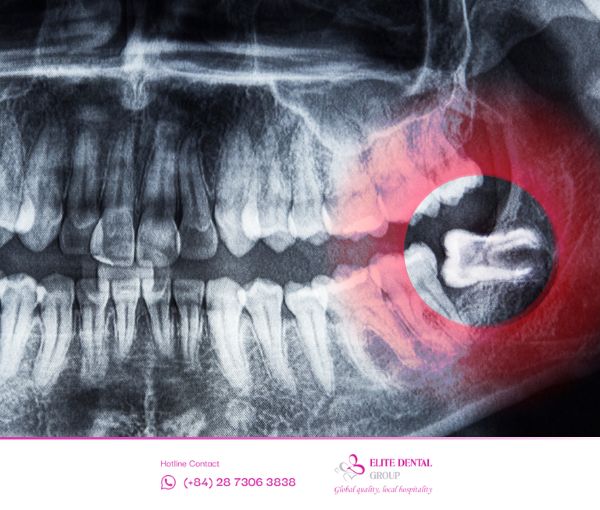

Răng khôn mọc ngang là tình trạng chiếc răng số 8 thay vì mọc thẳng đứng theo trục của cung hàm thì lại mọc theo phương nằm ngang (góc 90 độ so với răng số 7).

- Cơ chế: Thân răng thường đâm thẳng vào chân răng hoặc thân răng số 7 bên cạnh.

- Phân loại: Ngoài mọc ngang hoàn toàn, răng khôn còn có thể mọc nghiêng gần (hướng về răng số 7), nghiêng xa (hướng về phía sau hàm) hoặc mọc ngầm hoàn toàn trong xương hàm.

- Khi phim chụp X-quang/3D cho thấy răng đang có xu hướng đâm ngang, có nguy cơ gây u nang hoặc tổn thương dây thần kinh.